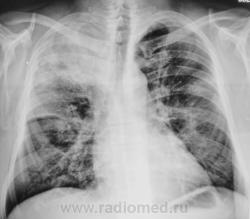

Томограммы.

Валентин Львович и так все знает, что делать, поэтому советовать ничего не буду, только скажу, что пока я за пневмонию.Инфильтрация больше пневмоническую напоминает,междолевая плевра отреагировала,

В клинике тоже,думаю, проявления неспецифического процесса преобладают.

не видно, по крайней мере мне, тут абсцедирования

А, я, наверно поспешил, абсцедирование в протокол забацал.